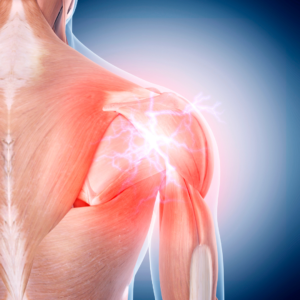

Are stiff joints or discomfort limiting your mobility? Whether it’s your knees, shoulders, or hips, joint issues can make it harder to stay active and enjoy life.

At Prolean Wellness, we offer regenerative wellness solutions designed to support your body’s natural recovery processes. These innovative, non-invasive therapies may help promote joint flexibility, encourage movement, and assist in long-term wellness—without surgery or extended downtime.

Our advanced wellness therapies use biologically active components to support natural tissue function and recovery. These treatments are designed to complement your body’s own healing mechanisms, providing a proactive approach to maintaining joint health and mobility.